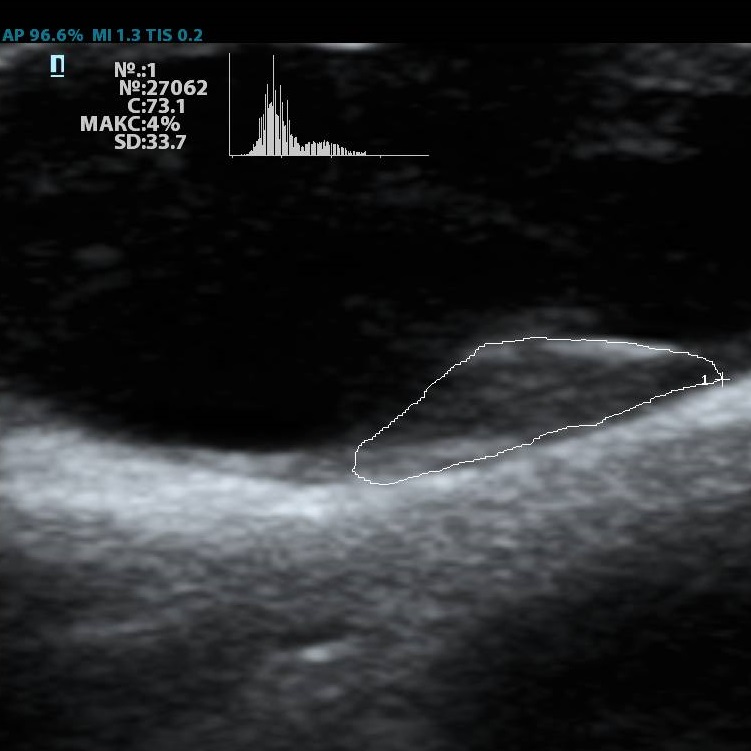

Обзор функций УЗИ: Компьютерный анализ структуры бляшки (показатель GSM)

Помимо базовых целей по выявлению атеросклероза, бляшек, оценки кровотока и значимости стеноза, врачу ультразвуковой диагностики ставится и множество других задач при исследовании сонных артерий. Одна из них – оценка стабильности бляшки.

Ранее коллеги опирались на визуальную оценку, насколько бляшка гомогенная и какова её эхогенность. Есть ли в ней кальцинаты или анэхогенные участки. Для этого использовались международные классификации, с разделением среза бляшки по процентам – сколько гипер- и сколько гипоэхогенных зон. Такой метод оценки до сих пор весьма популярен, однако он имеет минусы. Основной его минус в субъективности. Тяжело на глаз сказать, на 49,9% своей площади бляшка эхогенна или же на 50,1%, да и глаз у каждого человека несколько разный. Один специалист скажет – тут больше 50% гипоэхогенного, другой, что менее. Таким образом, метод сильно зависит от оператора – специалиста ультразвуковой диагностики.

Современное решение – компьютерный анализ структуры бляшки. Ультразвуковая система экспертного класса Mindray DC-8 способна провести программный анализ полученного изображения бляшки и дать количественную оценку её структуры. Для этого используется показатель GSM – Grey Scale Median. Прибор рассчитывает медиану по показателям серой шкалы в выделенной зоне и выдает данные в виде графика распределения эхогенности и числовых данных для количественной оценки. Таким образом, исследование становится более объективным и воспроизводимым, снижается зависимость от оператора (человеческого фактора).